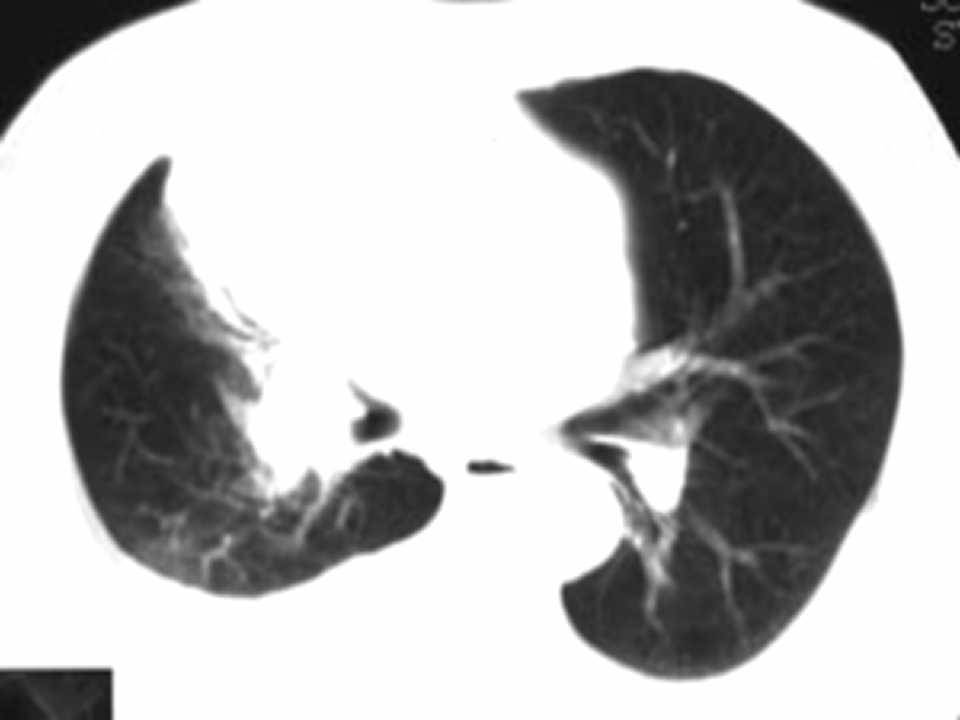

肺癌影像学表现